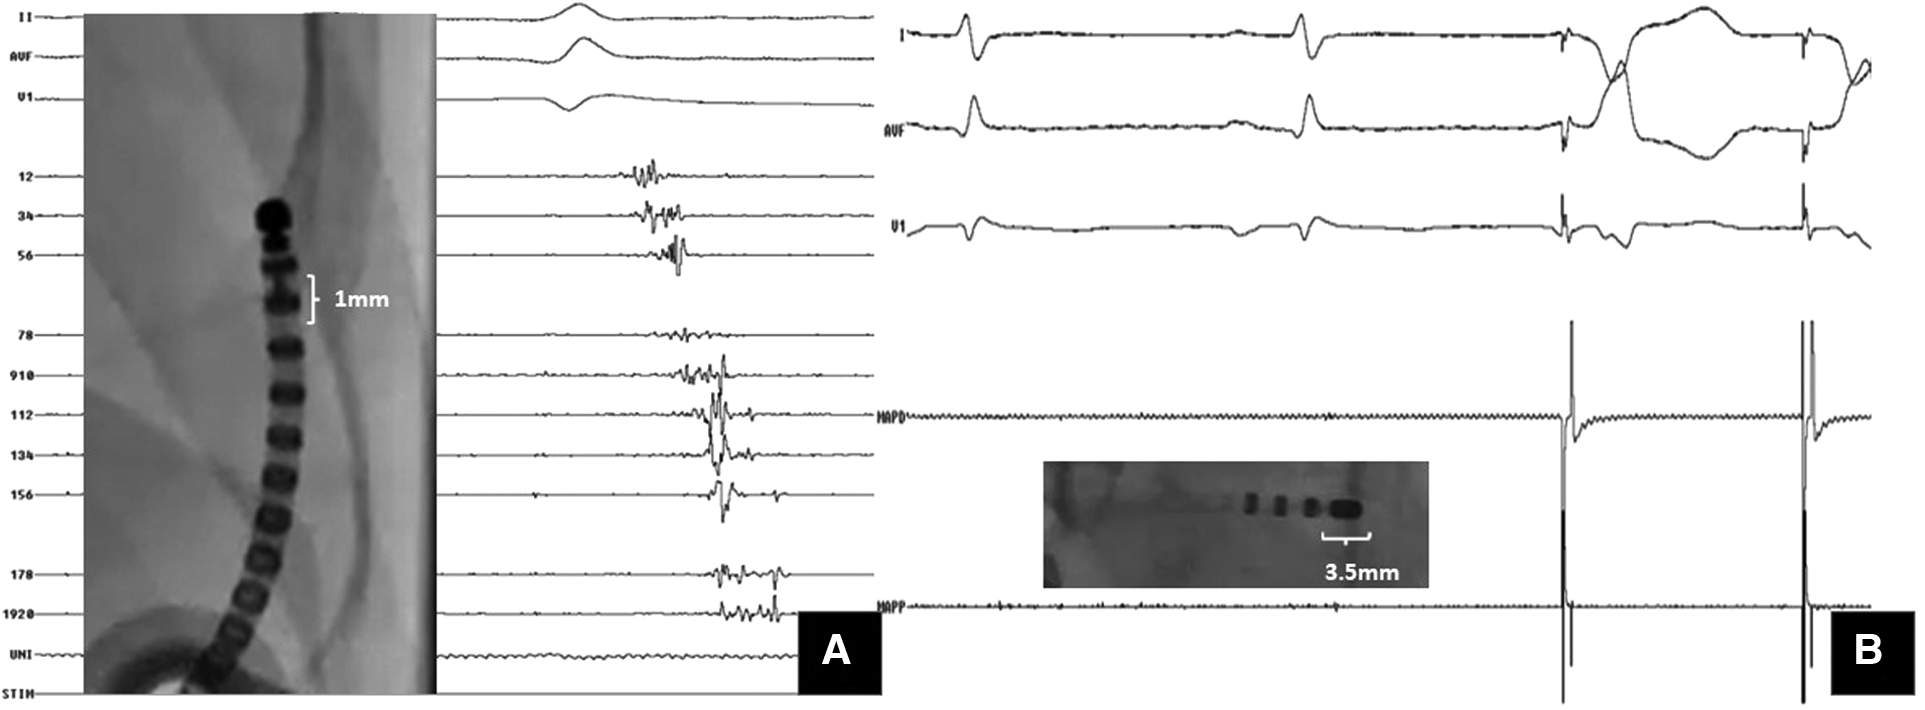

Figure 2

Importance of multielectrode mapping. A Case of ARVC with VT storm: substrate mapping with (A) multipolar catheter (1 mm electrode size) showed isolated late potentials within the scar; (B) mapping with the ablation catheter (3.5 mm tip electrode) at the same site could not pick up these signals. However, pacing at same site captured with latency.

Current substrate-based ablation strategies emphasize the need for high density mapping to identify and target all multicomponent electrograms. High density multi-electrode mapping has brought about a paradigm shift in substrate characterization during VT ablation. Local electrogram voltages are dependent on the recording electrode size, inter-electrode spacing, and direction of wavefront propagation (68). The use of multi-electrode mapping catheters with small (1.0 mm) closely spaced electrodes resulted in a 22% smaller low voltage area (<1.5 mV) and a 47% reduction in dense scar size (<0.5 mV) in animal models (69, 70). Another advantage of these high-density catheters is that they minimize the effects of far-field signals and aid in the identification of heterogeneity within low-voltage scars. Higher mapping densities are associated with a better endocardial LAVA identification and ablation outcomes.